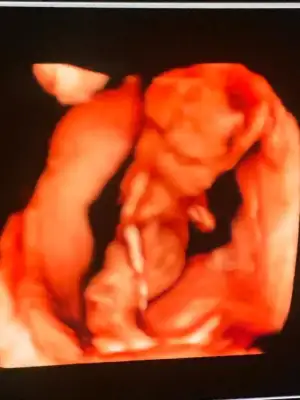

Teyzeler merhaba biz geldik 💖 her şey yolunda çok şükür

Eklentiler

• f009a477-a1a1-4e24-9f8f-2fa05036ad4f.webp

f009a477-a1a1-4e24-9f8f-2fa05036ad4f.webp

22,2 KB · Görüntüleme: 84